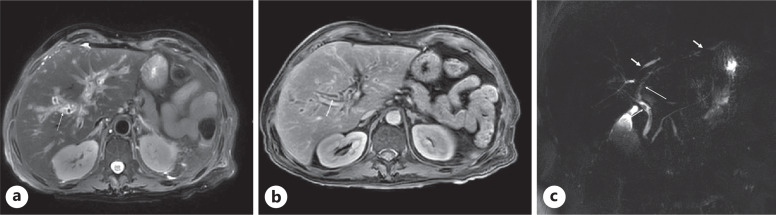

Case presentation: A 60-year-old male patient with multiple comorbidities presented with fever, chills, and cough for 1 day. In the emergency department, he tested positive for COVID-19 by PCR and his chest X-ray revealed features suggestive of pulmonary edema. The patient was intubated and admitted to the Medical Intensive Care Unit (MICU) for management of COVID-19 pneumonia with pulmonary edema. During hospitalization, he developed cardiac complications that required targeted management. Approximately 1 week after admission, his liver enzymes began to rise. Although drug-DILI was initially suspected and hepatotoxic medications were discontinued with the initiation of ursodeoxycholic acid (UDCA), the liver function tests (LFTs) remained elevated. Subsequent magnetic resonance cholangiopancreatography revealed periportal inflammation with intrahepatic biliary dilatation and stricturing, findings consistent with COVID-19 induced cholangiopathy. The UDCA dosage was doubled, resulting in gradual biochemical improvement; however, the patient ultimately discharged against medical advice.